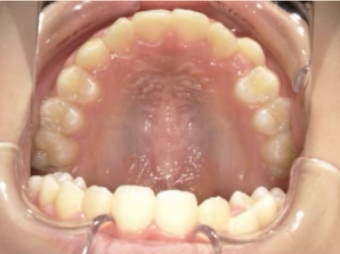

治療中⑨ 中3:14y4m

モノブロック装置で左上八重歯が改善しました

今後、必要によりマルチブラケット法へ移行予定です